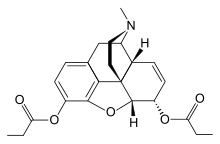

- Esters of morphine opiates: slightly chemically altered but more natural than the semi-synthetics, as most are morphine prodrugs, diacetylmorphine (morphine diacetate; heroin), nicomorphine (morphine dinicotinate), dipropanoylmorphine (morphine dipropionate), desomorphine, acetylpropionylmorphine, dibenzoylmorphine, diacetyldihydromorphine;[261][262]